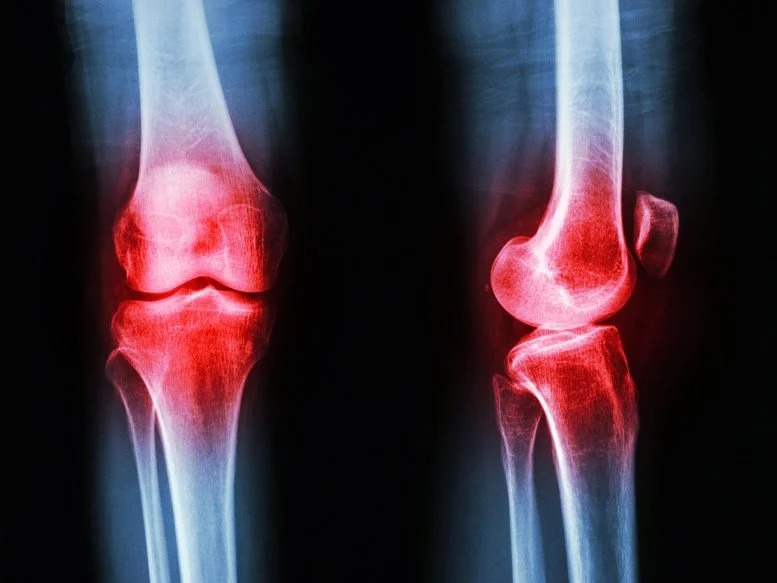

La clave del movimiento reside en el cartílago, el tejido que amortigua los huesos. A diferencia de otros tejidos, el cartílago no tiene suministro de sangre y depende casi totalmente del movimiento para recibir nutrientes. Al caminar o realizar actividades, el cartílago se comprime y libera fluidos, funcionando como una esponja que expulsa desechos y absorbe nutrientes frescos. Esto desmiente la idea de que la artrosis es un simple desgaste por uso, ya que las articulaciones no son estructuras pasivas, sino sistemas que requieren estímulo para mantenerse sanos.